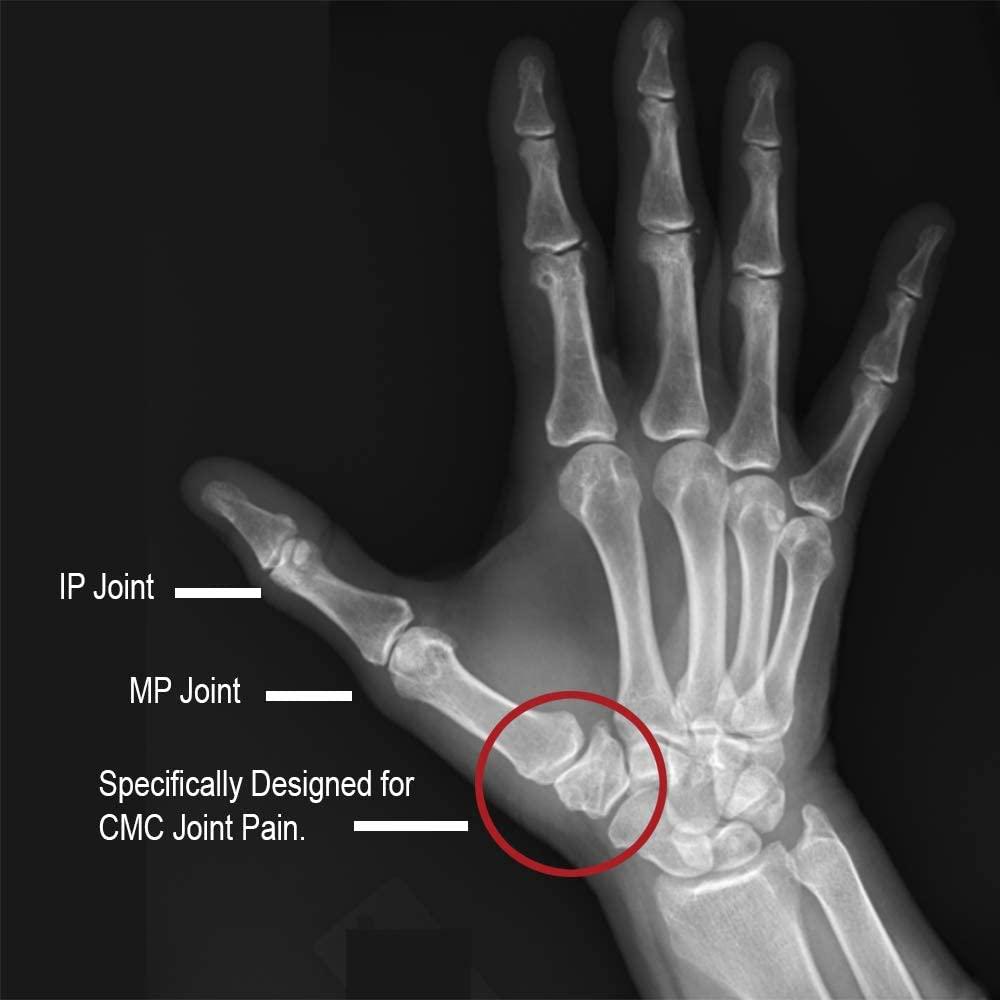

Comfort Cool Thumb CMC Restriction Splint. Patented Thumb Brace Thumb Splint For Dislocation For more severe sprains or tears of the ligament, surgery may be needed to restore stability to the joint. Phalanx dislocations are common traumatic injury of the hand involving the proximal interphalangeal joint (pip) or distal interphalangeal joint. List includes best home remedies & exercise suggestions from pts. Understanding the pathophysiology of thumb cmc joint dislocations is important in determining. Thumb Splint For Dislocation.

CMC Thumb Splint Thumb CMC Joint BeneCare Direct Online UK Shop Thumb Splint For Dislocation List includes best home remedies & exercise suggestions from pts. For more severe sprains or tears of the ligament, surgery may be needed to restore stability to the joint. Diagnosis is clinical and can be confirmed by orthogonal radiographs. Understanding the pathophysiology of thumb cmc joint dislocations is important in determining appropriate management. Your doctor probably put the thumb back. Thumb Splint For Dislocation.